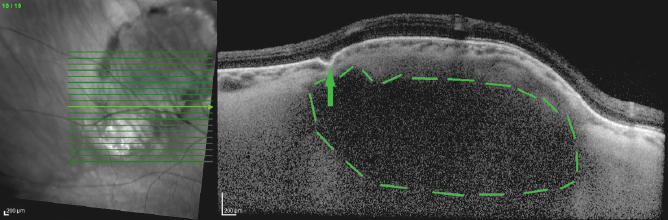

In our cases, the acquired tomographic signs were characteristic of SCC, namely the chorioretinal complex elevation with an uneven tuberous surface, the presence of a “peak-shaped” contour of the Bruch’s membrane, a choroid thinning with increased signal hyperreflectivity, the presence of damage zones in the Bruch’s membrane, disorders of the retinal architectonics (thinning due to atrophy of the retinal outer layers in the zones of the Bruch’s membrane “peak-shaped” contour and an increase in the retinal thickness because of expansion of the nuclear layers in the Bruch’s membrane retraction zones) (Figs. 3, 4). Under the thinned choroid, zones of a local moderately hyporeflective structure were visible (Fig. 5), which is considered as a distinct sign of scleral inner layers lesions [3]. Furthermore, the visualization of the outer border of the choroid was disturbed in the areas of the retinal lesion.

Fig. 5. Optical coherence tomography of the patient Sh. (59 years old). Horizontal scan across sclerochoroidal calcification. Arrow – thinning of the choroid and the zone of Bruch’s membrane “entrapment”; dotted line – hyporeflective structure under a thinned choroid

Рис. 5. Оптическая когерентная томография пациентки Ш., 59 лет, горизонтальный срез через зону склерохориоидальной кальцификации. Стрелка — резкое истончение хориоидеи и зона «западения» мембраны Бруха; пунктир — гипорефлективная структура под истончённой хориоидеей